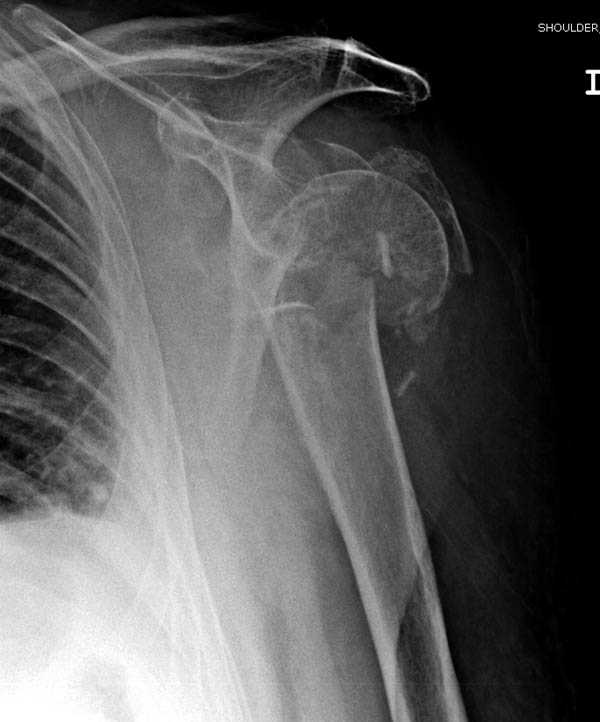

Пациентка Б.1953 г.р., врач-терапевт. Травма 27.11.08г. Падение с высоты роста. Выявлен закрытый не осложненный оскольчатый перелом хирургической шейки левого плеча со смещением. 02.12.08г. оперирована. Выполнена открытая репозиция и остеосинтез пластиной LCP Деост с дополнительной фиксацией отдельно лежащего фрагмента винтом. Послеоперационный период протекал без особенностей, заживление раны первичным натяжением. Швы сняты через 10 дней. Иммобилизация левой верхней конечности клиновидной подушкой 4 недели. По окончании срока – рентген-контроль и умеренная разработка плечевого сустава. В течении месяца функция левого плечевого сустава восстановилась удовлетворительно: поднятие руки до 110 гр., отведение - 90 гр. и до 110 гр. отведение с лопаткой. Отведение руки назад – 20 гр. Наружная и внутренняя ротация – 20 гр. Пациентка по настоянию самостоятельно вышла на работу. 27.03.09 при контрольном осмотре жалоб не предъявляет, болевой синдром в левом плечевом суставе отсутствует. Отведение плеча активно до 90 гр, пассивно с лопаткой до 110 гр., поднятие – 110 гр, отведение назад 20 гр, наружная и внутренняя ротация по 20 гр. На контрольных рентгенограммах отмечается смещение металлоконструкции, ротация головки плеча с приведением дистального отломка на 13 гр. и смещением к зади на 30 гр. Рентгенограммы прилагаются. Ваш взгляд на дальнейшую тактику лечения пациентки?

Рентгенограммы действительно с дефектом укладки, но интраоперационная репозиция, можете поверить, была удовлетворительная как в акcиальной, так и в сагиттальной плоскостях. Интраоперационная рентгенограмма прилагается, хотя укладка тоже на ахти. По тактике - разделяю Ваше мнение об отсутствии необходимости реостеосинтеза, а тем более об эндопротезировании, хотя это все было предложено пациентке ведущими ортопедами-травматологами России.

Ошибки встречаются тогда, когда удовлетворяются только одной проекцией рентгена.

Здесь пример открытой репозиции 57 летнего с переломом плеча (1,2) смещение обнаружено на интероперационном снимке. При нормальной прямой проекция (3) угловое смещение обнаружили в аксиальной проекции (4)